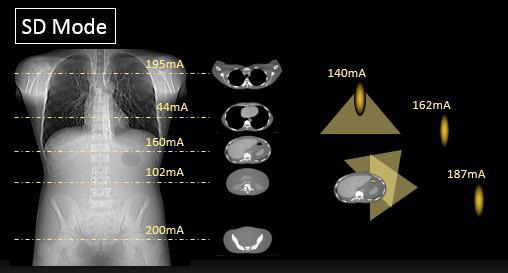

采用了最先进的驱动技术,极大的提高了信号的传输效率,确保进行快速的扫描。 机架采用标准几何设计,射线扇形角小。 机架上横断位,矢状位,冠状位三个方向定位灯,确保定位的快速准确。 采用呵护患者的先进设计,机架开口径达 750mm。